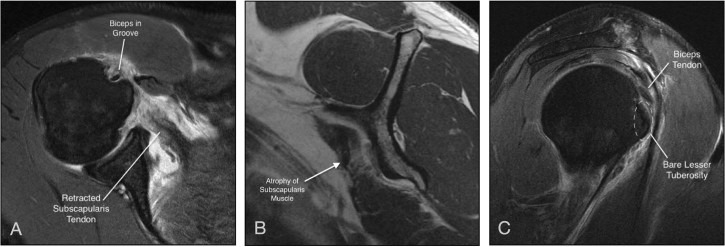

Specific intra-articular findings have been described to prompt the surgeon to eval‎uate the subscapularis tendon carefully. The most obvious is complete medial dislocation of the tendon of the long head of the biceps (Fig. 3). Partial tearing of the medial biceps as it exits the joint has been termed “sentinel sign” by Lafosse and colleagues, indicating a high-likelihood of partial-thickness subscapularis tearing.56 Medial retraction and adoption of a comma sign by the interval ligaments has also been described as an indicator of subscapularis tearing.40

Figure 3.

Open in a new tab

Medial dislocation of the long head of the biceps tendon.